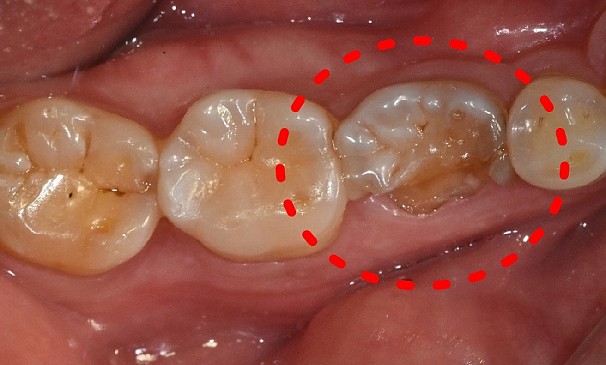

김OO님 전후사진 | 치료 기간 : 3주

치료 전

치료 후

치아머리 확보술